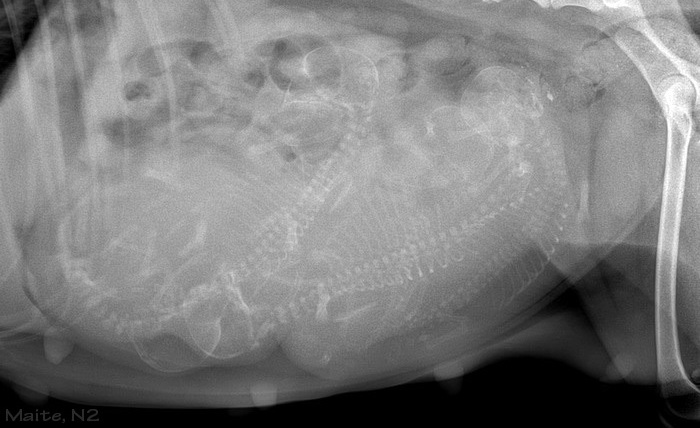

1 Woche vor Termin

Maite

Conner